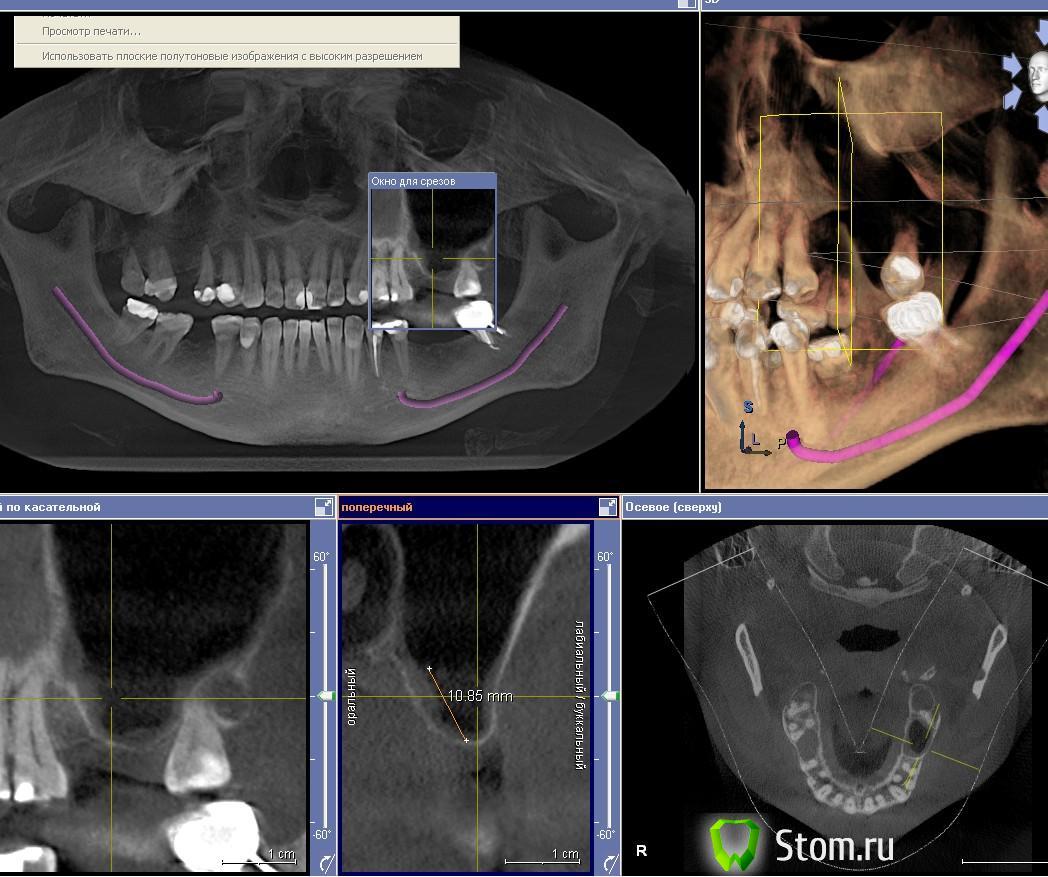

Poul Опубликовано 25 апреля, 2012 Автор Поделиться Опубликовано 25 апреля, 2012 (изменено) Вот как профи, скажите, это - хорошо делают?Я вот не вижу верхней границы кости Изменено 25 апреля, 2012 пользователем Poul Ссылка на комментарий

samsonov Опубликовано 25 апреля, 2012 Поделиться Опубликовано 25 апреля, 2012 Вас какая кость скелета интересует?По единичному скриншоту оценивать что-то некорректно.10,85 мм- это вы измеряете внутри пазухи... Ссылка на комментарий

Bier Опубликовано 25 апреля, 2012 Поделиться Опубликовано 25 апреля, 2012 Вот как профи, скажите, это - хорошо делают?Я вот не вижу верхней границы кости так там кости 0,5мм верхней границы там где вы замеряете и нет. Ссылка на комментарий

Poul Опубликовано 27 апреля, 2012 Автор Поделиться Опубликовано 27 апреля, 2012 samsonov Bier Я понимаю что измерения скорее всего внутрь пазухи. Я про качество томографии. Такое качество - это нормально? А если нормально, как вы определяете границы кости? Ссылка на комментарий

samsonov Опубликовано 27 апреля, 2012 Поделиться Опубликовано 27 апреля, 2012 Вы хотите получить краткий курс рентгенологии,простите?Хотите сами заказать импланты себе? Имхо,достаточно информативно. Ссылка на комментарий

Bier Опубликовано 30 апреля, 2012 Поделиться Опубликовано 30 апреля, 2012 samsonov Bier Я понимаю что измерения скорее всего внутрь пазухи. Я про качество томографии. Такое качество - это нормально? А если нормально, как вы определяете границы кости?ну по мне так там видно все границы, необходимые для стоматологического лечения. А если вы хотите увидеть верхнюю границу гайморовой пазухи, так знайте, что она не вошла в дентальный снимок, т.к. верхней стенкой пазухи является нижняя стенка глазницы. Ссылка на комментарий